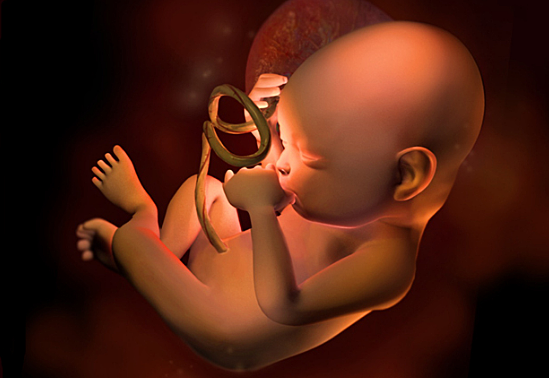

El bebé ya se mueve dentro de la mujer y ya es capaz de estirarse y dar pequeñas pataditas. Si es el primer embarazo aún es pronto para que las mujeres noten esta sensación de hormigueo . Pero las mujeres que ya tienen su segundo embarazo ya pueden sentir esta sensación alrededor de las 12 semanas. Él bebe ya puede tener 10 semanas de vida y mide 6,5 centímetros y pesa 18 gramos. Él bebe ya se pude alimentar a través del cordón umbilical, recibiendo ya nutrientes y oxigeno

• Semana de la 13 a la 14

Semana de la 13 a la 14

El bebe en estas semanas ya se le podrán ir formando mejor los órgano y su cabeza todavía no tendrá forma ,aunque en estas semanas ya comenzara a funcionar el sistema nervioso y pesara 20 a 25 gramos, medirá de 7 o 8 cm